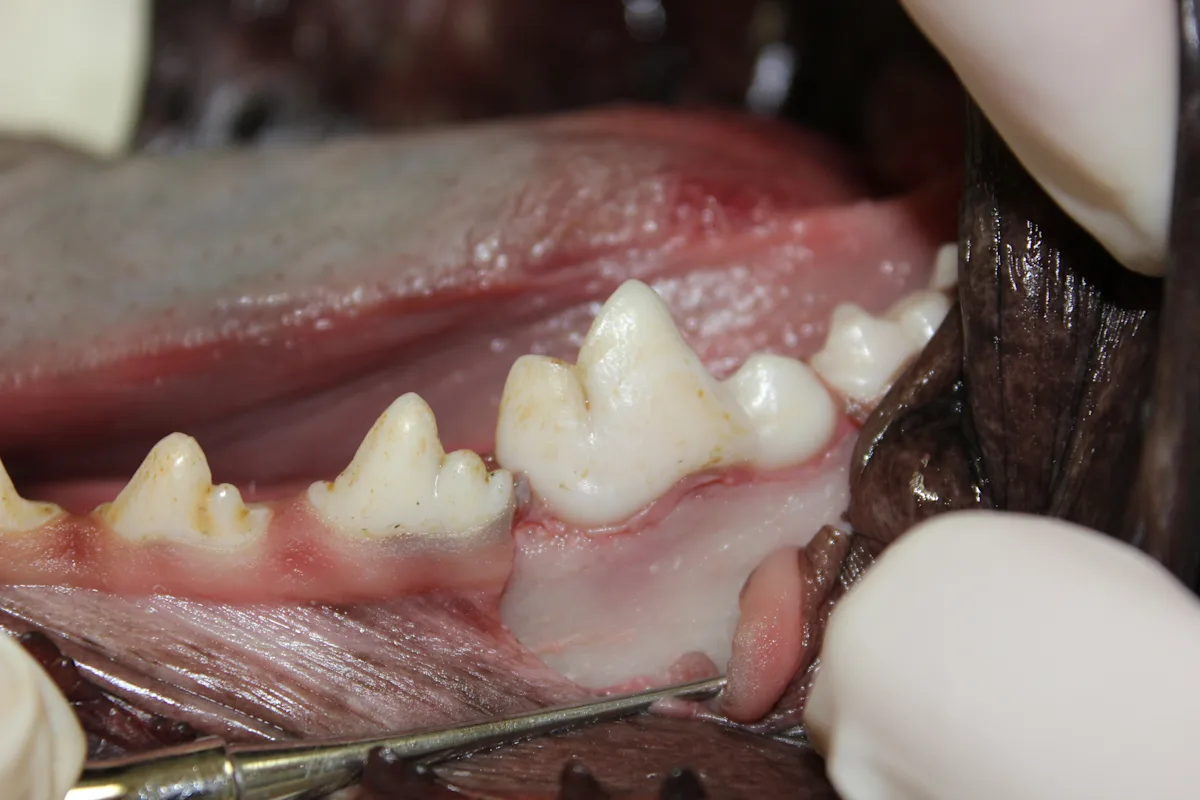

(A) Section the tooth at the furcation with a #701L bur (cross-cut taper fissure bur) in the water-cooled high-speed handpiece. Place the bur in the furcation perpendicular to the root axis. Once the bur has passed through the alveolar bone, advance it in a coronal direction until it is completely through the crown. (B) To determine complete section of the crown, place a dental elevator between the sectioned segments and rotate it gently. If the 2 segments move independently, the crown has been completely sectioned.